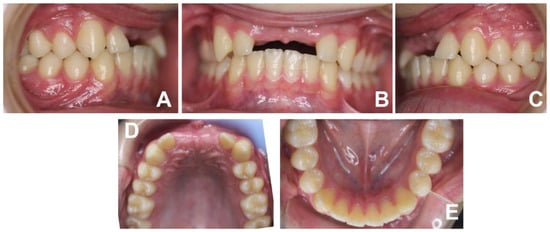

3. Results

4. Discussion